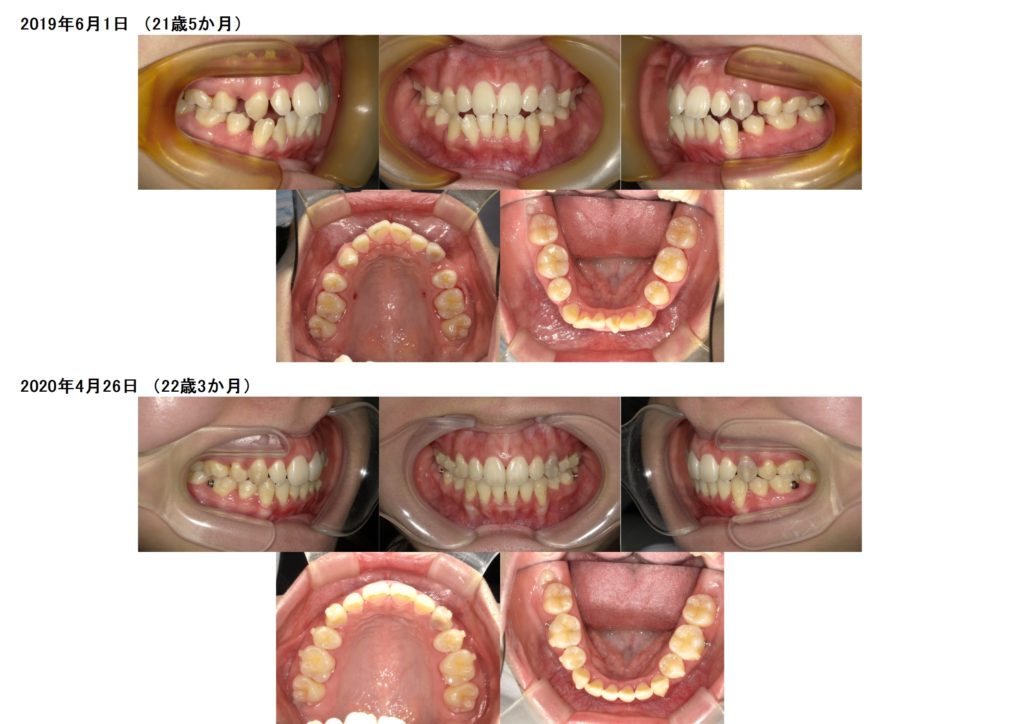

抜歯の治療例の写真

↑抜歯、突出ケースでもしっかりとマウスピースを使うとこんなに早く変化が分かります。ここから再度噛み合わせの微調整に入るためのマウスピースを作成します。

↑ほんの細かいことですが、しっかりとゴールを迎えるために何度もポイントポイントでマウスピースの発注を行い、ゴールへと向かいます。